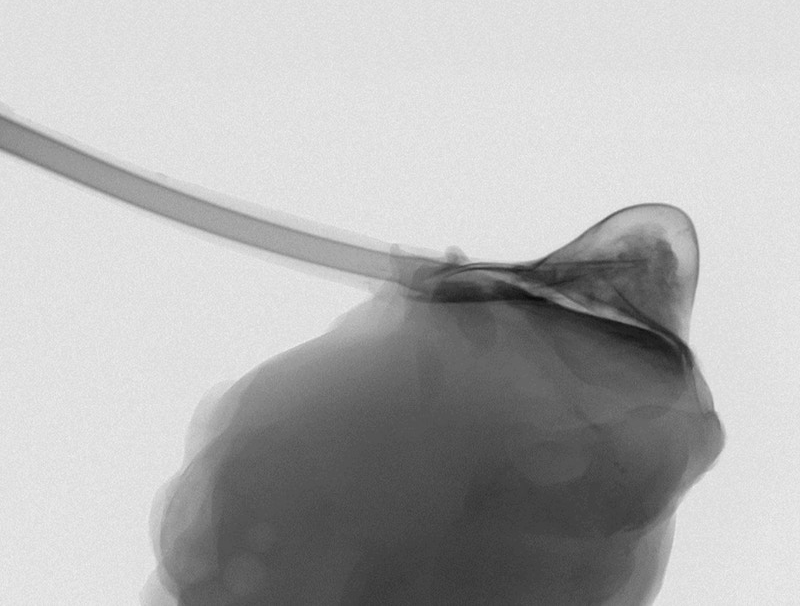

Therepi - fatto di un polimero gelatinoso a forma di semisfera con la parte schiacciata che si attacca al cuore - può anche rilasciare cellule per veicolare terapie cellulari che riparano il cuore nelle aree danneggiate da infarto. «Dopo un infarto potremmo usare questo apparecchio per rilasciare terapie preventive contro l'insorgere dell'insufficienza cardiaca», spiega Ellen Roche, coautore del lavoro del MIT, Institute for Medical Engineering & Science.